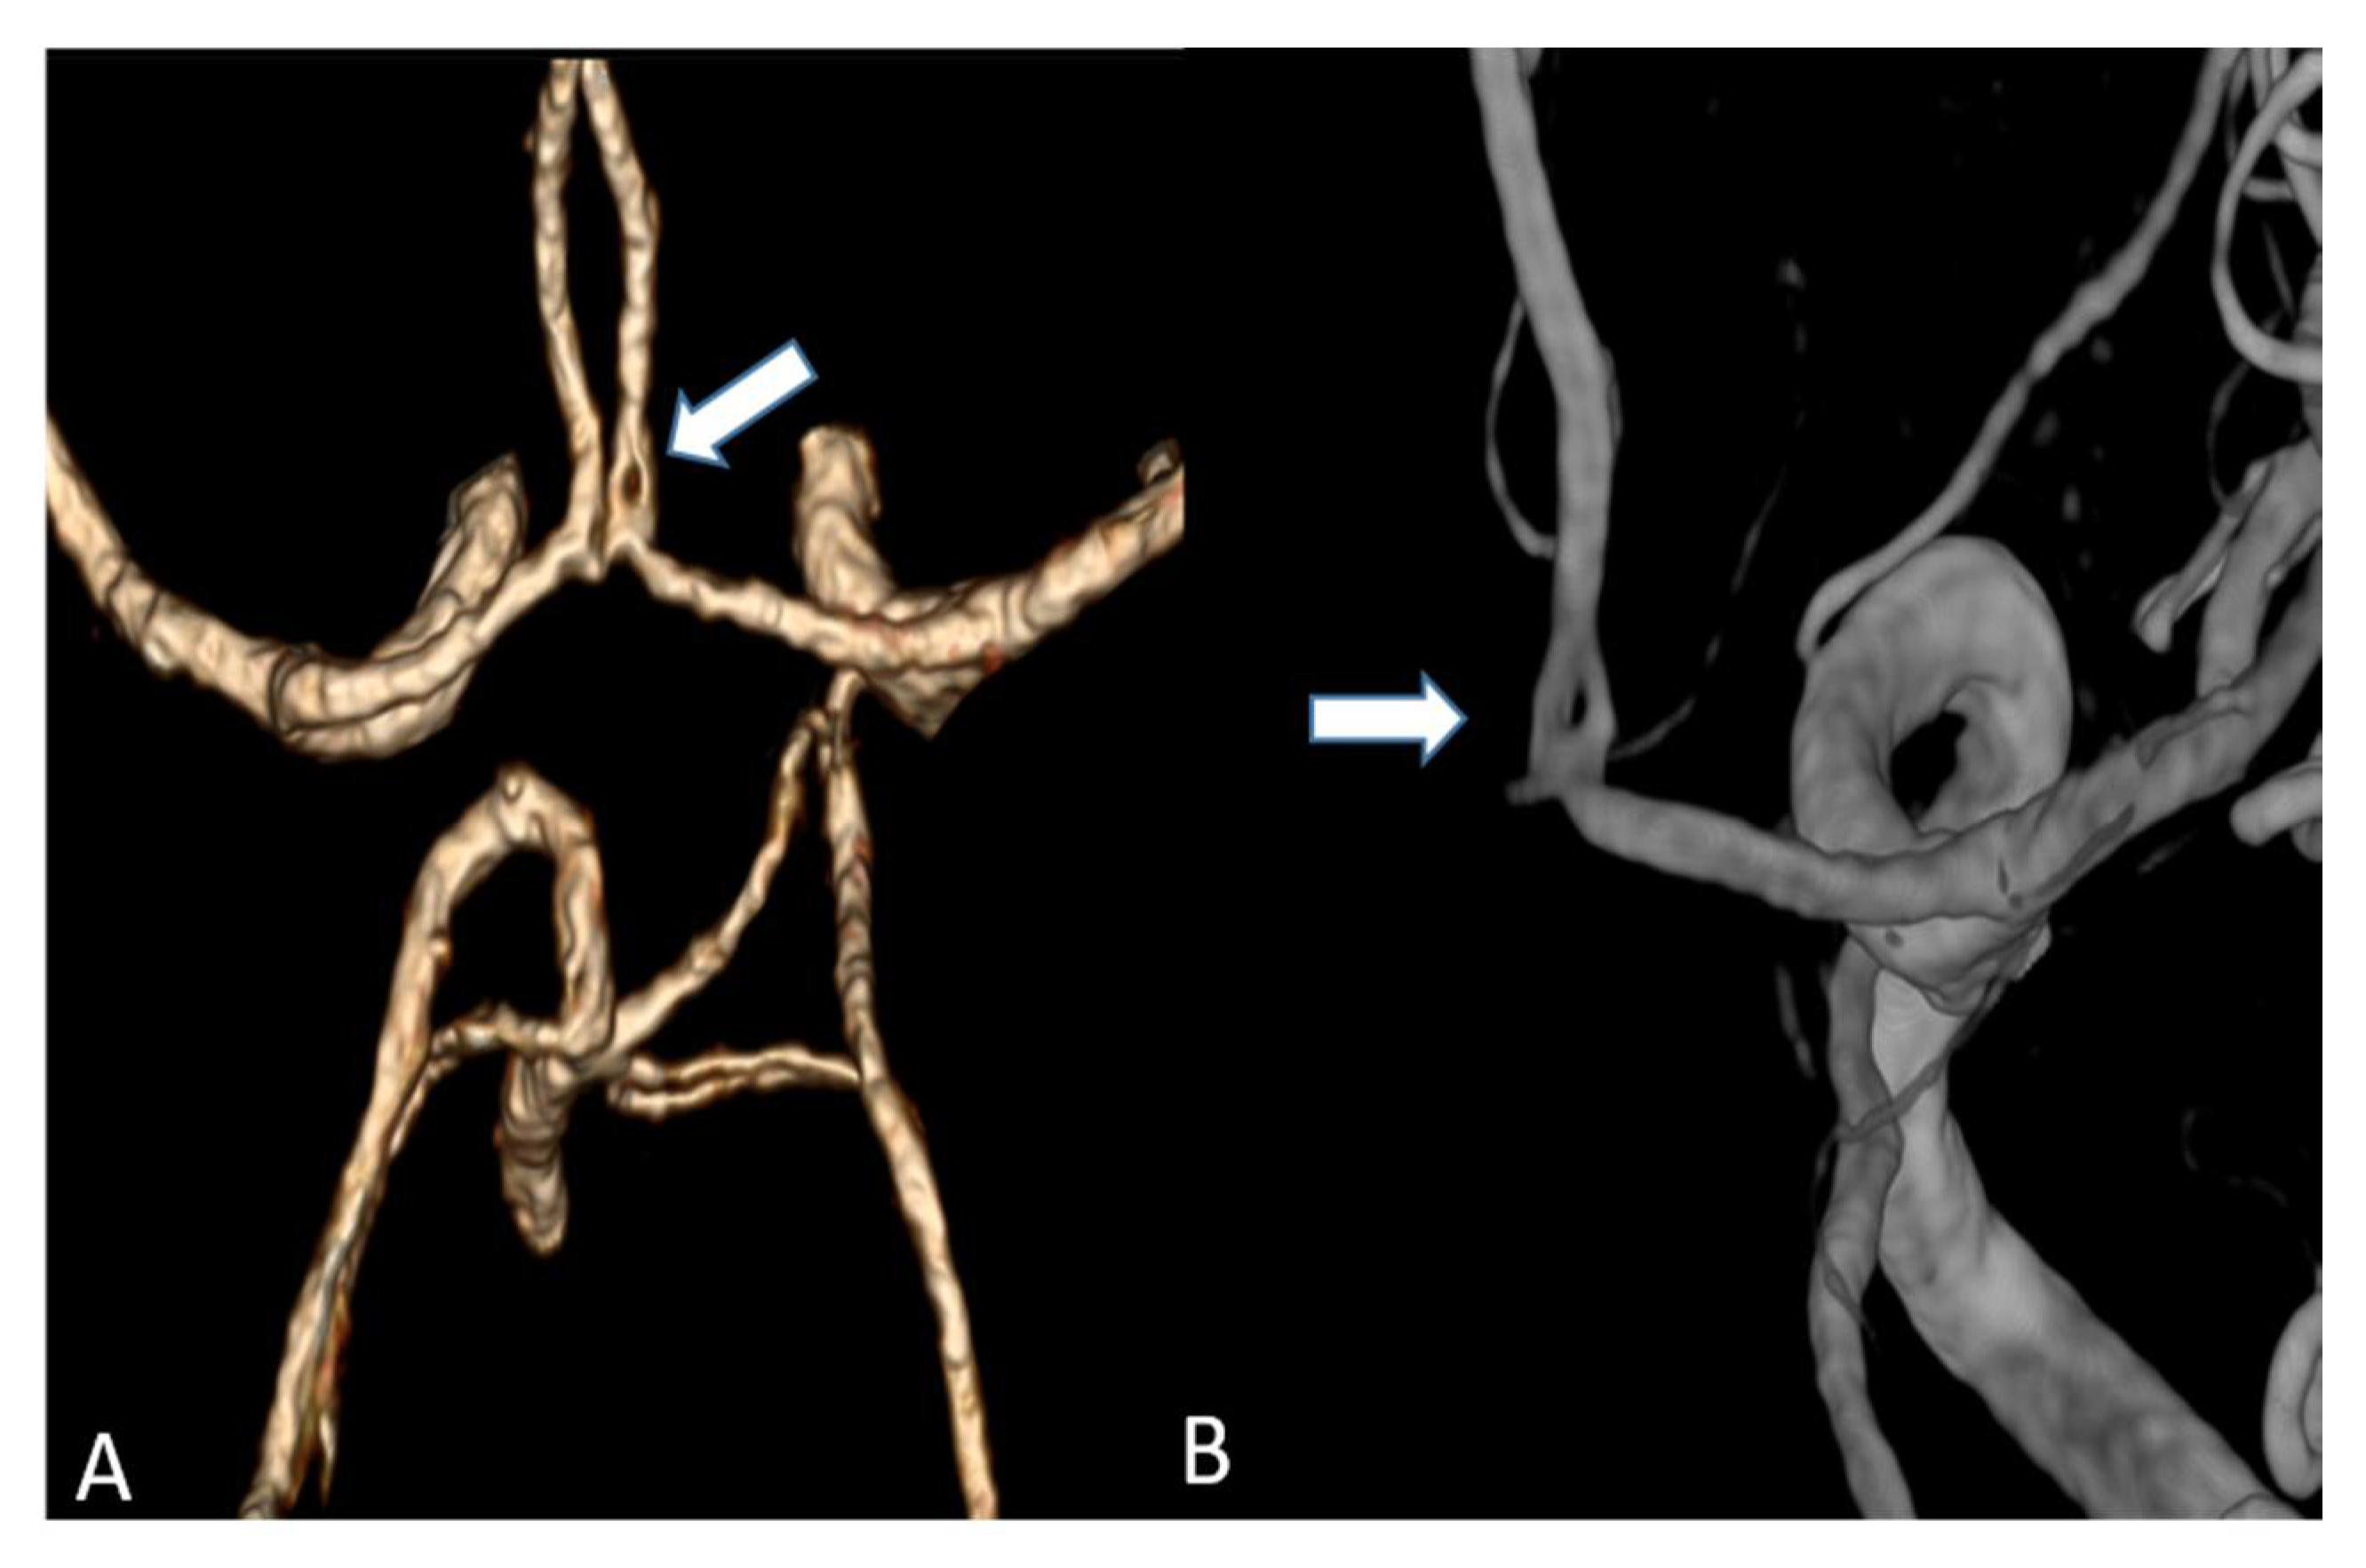

Figure 4.

Maximum intensity projection of a supra-aortic UHR-CTA, (A) coronal projection showing an internal carotid artery plaque (white arrow) as well as contrast and delineation of, e.g., the thyrocervical trunk; (B) sagittal projection.

(A) Volume rendering of an anterior cerebral artery fenestration acquired by an UHR-CT (B) Three-dimensional (3D) digital subtraction angiography (DSA) to confirm arterial fenestration in (A), which is often not detected by normal resolution CTAs.

In summary, the subjective analysis of all images showed excellent results for the applied qualitative parameters such as overall image quality, overall contrast noise and artefacts, the latter focusing on streaks within the posterior fossa. A high-rated vessel contrast and delineation could also be observed, which were not only limited to the large cerebral vessels but also appeared in the smaller vessel sections, especially in the deep cerebral perforators (e.g., lenticulostriate arteries). Patient examples are given in Figure 2, Figure 3, Figure 4 and Figure 5. Interrater reliability was ascertained by applying Cohen’s kappa coefficient and showed a fair agreement (k = 0.26).

Studies on coronary artery and small visceral artery CTAs [11,12] have recently shown that the UHR-CT system is highly suitable for a significant improvement in image quality, SNR, CNR and an enhanced vascular imaging. Our investigation, which to our best knowledge represents the first study to evaluate image quality, contrast and delineation of the supra-aortic vessels and the small perforating arteries, confirms the excellent qualification of the UHR-CTA as a diagnostic tool in radiological and vascular imaging. Hence, the use of UHR-CTA will be of high value in various clinical settings, especially when a high resolution is inevitable for an accurate diagnosis and optimized patient care. In detail, advances in the diagnosis of aneurysms and steno-occlusive diseases may be reached, especially when looking at aneurysm configuration, and peculiarities or irregularities of the of aneurysm wall. UHR diagnostics may additionally improve pre-invasive planning of subsequent digital subtraction angiographies and interventions, enabling earlier and more individualized treatment decisions. An additional benefit will arise from a substantially reduced radiation exposure due to the omission or the time reduction in follow-up examinations.